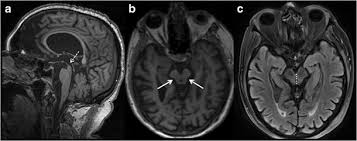

panda sign

symmetric hyperintensities of putamen > caudate, thalamus, brainstem; red nuclei are eyes

wilson’s disease

from copper deposition